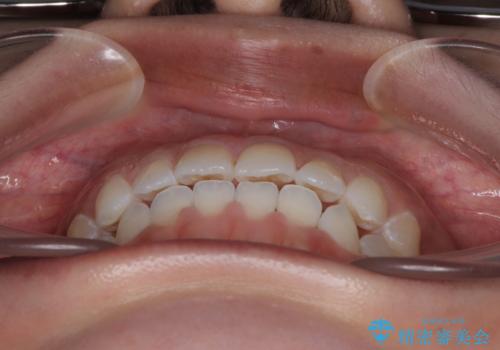

- 上下前歯のデコボコを気にして来院された患者様です。

ワイヤー矯正でもマウスピース矯正でも可能でしたが、短期間で、自身の手を煩わせることなく治療を行いたいとのことで、ワイヤー装置にて矯正治療を行うこととしました。

僅か半年強、あっという間に治療を終えることができました。